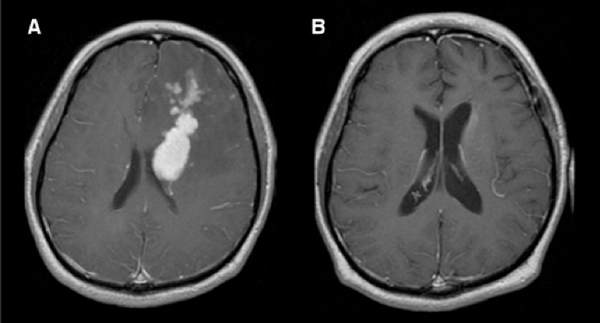

One of the unmistakable features of the disease, however, is its poor outcomes and its often severe and debilitating neurological symptoms. Unlike other forms of brain cancer, in which surgery is a front-line treatment, surgery is performed only to establish the diagnosis for primary CNS lymphoma because the tumors tend to be widely disseminated within the brain.